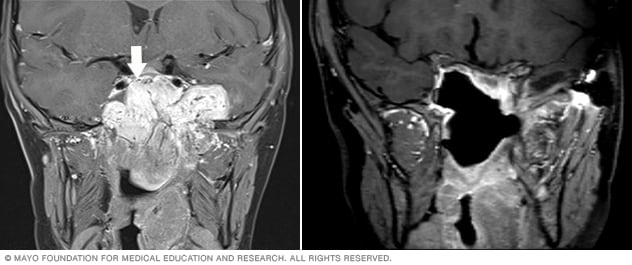

Two facial MRI scans showing the area of a juvenile nasopharyngeal angiofibroma before and after surgery.

Before surgery (left), a very large tumor — a juvenile nasopharyngeal angiofibroma (JNA) — is the white section at the center marked by the arrow. After surgery (right), the tumor is gone.